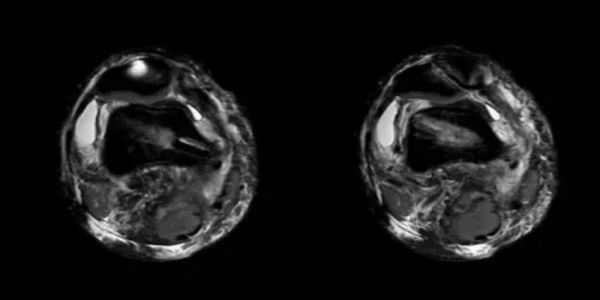

小赵女士在一次外出游玩时扭伤右膝关节,顿感膝关节疼痛不适,“打软腿”,就诊于当地医院CT检查提示关节积液。经熟人介绍来郑州大学五附院骨科一病区就诊,经主管医师张鹏飞仔细查体后,发现膝关节浮髌试验阳性,右侧髌骨内侧压痛,髌骨外推试验(+),恐惧试验(+),J-sign(+)。完善MRI等相关检查(见图1),证实为内侧副韧带(MPFL)完全撕裂。仔细追问病史,患者诉既往曾有过数次髌骨外移的症状,经休息后缓解,患者复发性髌骨脱位诊断明确。

图1 术前MRI检查